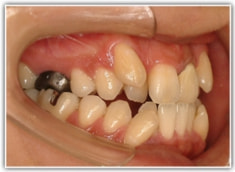

治療前

骨格的な下顎前突の傾向は強くはありませんが、歯牙の状態によって反対咬合が認められます。LowTongue(低位舌)もあります。

修復歯、補綴歯もあります。下顎8番が水平埋伏しています。